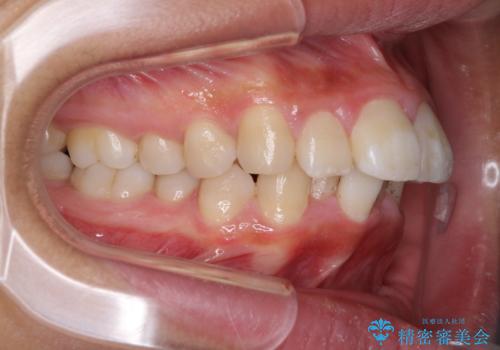

ワイヤーによる全体的ながたつきの矯正治療